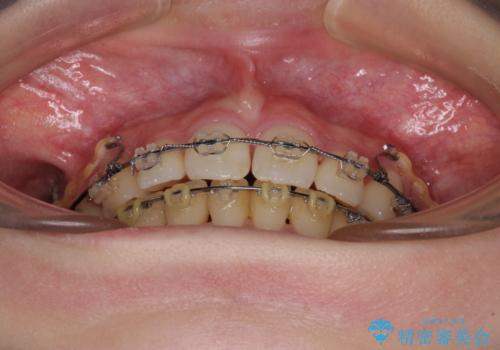

治療途中で転院 抜歯矯正の仕上げ治療

- 地元で抜歯治療を行っている途中、東京へ転職したため治療を継続して欲しいとのことで来院された患者様です。

出っ歯を抜歯矯正にて治療をしていらっしゃいましたが、抜歯スペースが少し残っていたため、閉じて歯列を仕上げていくこととしました。